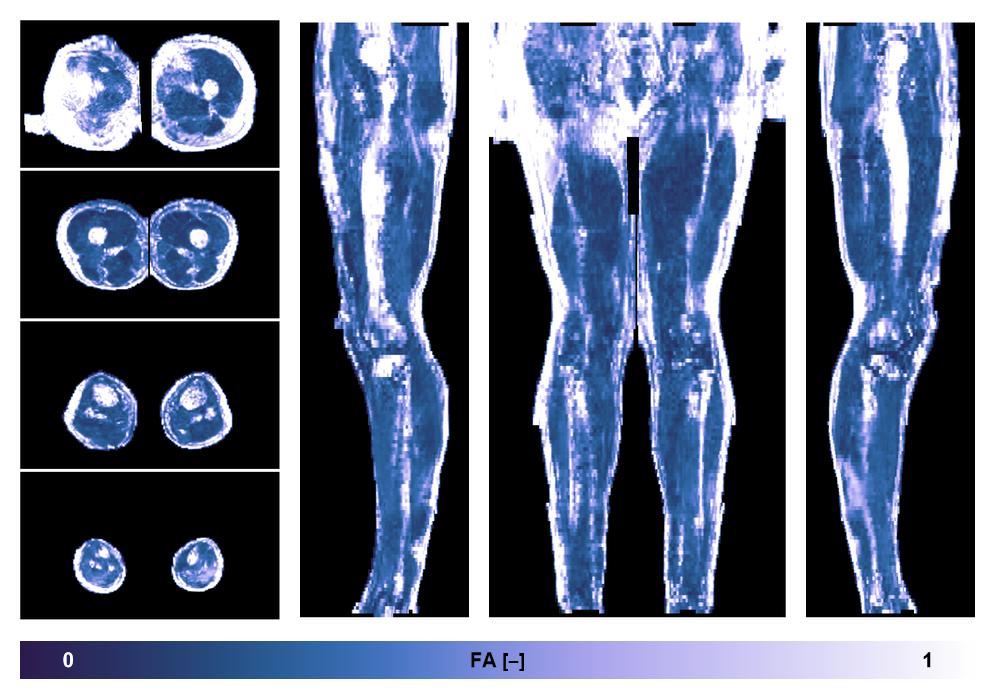

• Fractional anisotropy

IVIM corrected whole leg muscle fractional anisotropy obtained from diffusion tensor imaging.